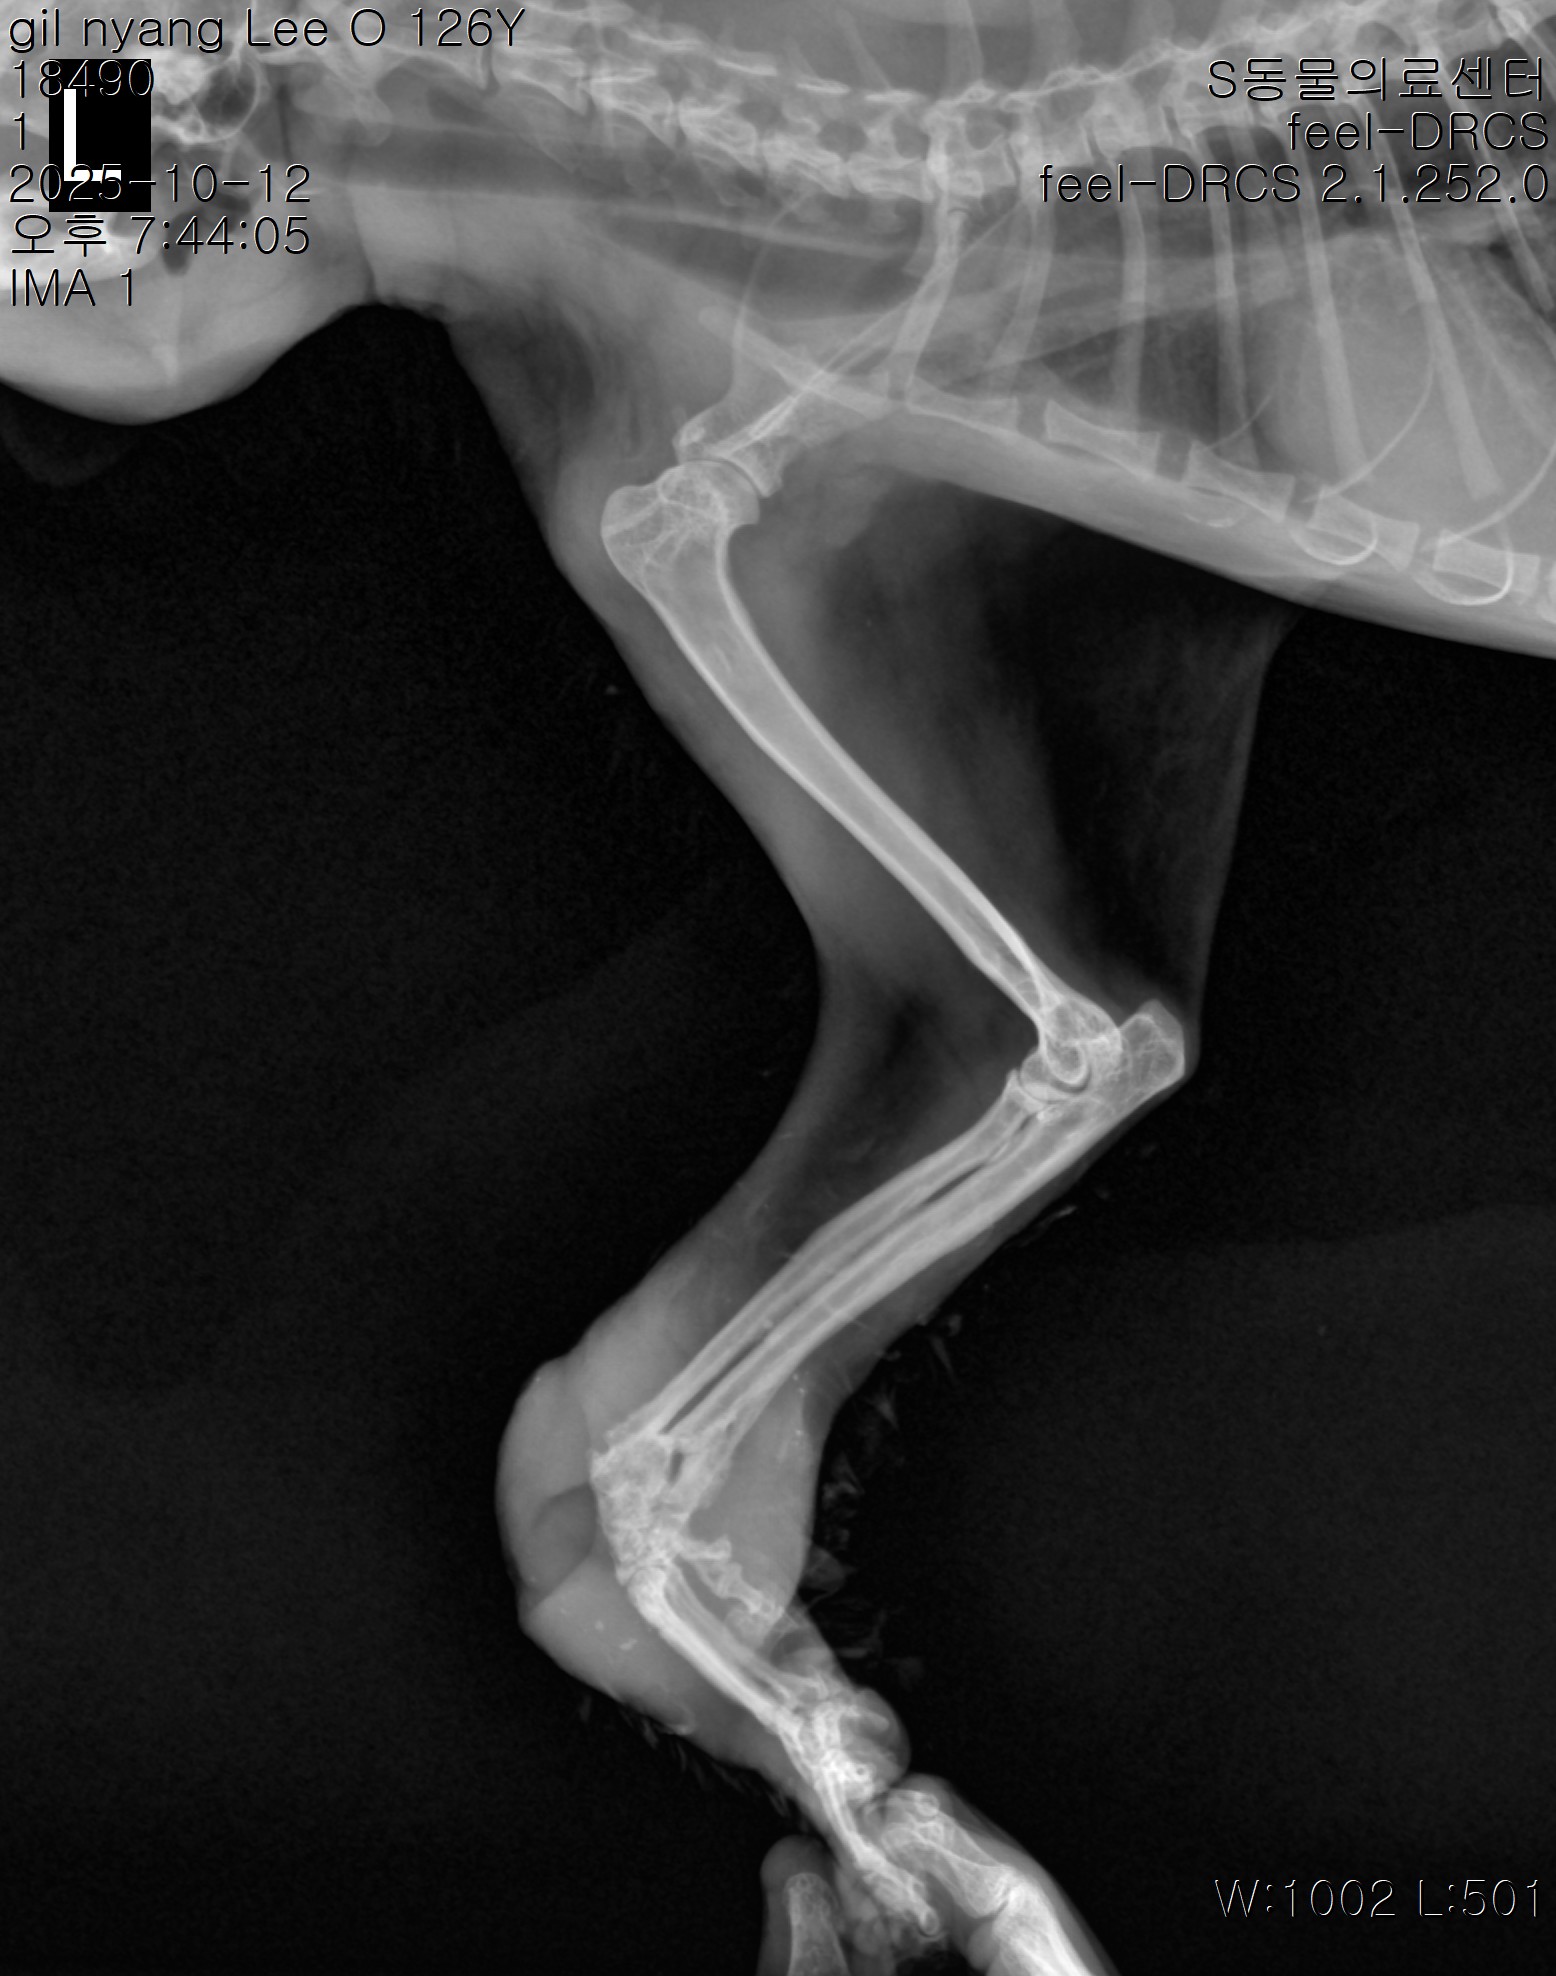

| 대상묘신청당시상태 | 찬이는 다리가 구부러져 고착화 되어있는 상태로 밥자리에 나타났습니다. 꺾인 앞다리를 들고 서 있었는데 부위가 빨갛게 살이 드러났습니다ㅠ 덩치에 비해 조금 마른것 같아 보이기도 했습니다. 사람을 크게 경계하지는 않았지만 그렇다고 친근하게 다가오진 않았습니다. 동네에서 보지 못했던 고양이였지만 가까이에서 보니 다리상태가 심각해 보였습니다. 앞발이 심하게 꺾여있었고 땅에 닿는 부위가 길에 쓸려 상처가 생긴 것 같았습니다. 입도 조금 아파하는 것 같았지만 일단은 다리 치료부터 해줘야할 것 같았습니다. 아픈 찬이를 구조하기로 결심을 하고 구조하였습니다. |

| 대상묘 병명 | 손목관절골절 |

| 치료과정 | 다리골절이 상당히 이전에 진행되어 그 상태로 자연유합 된 채로 굳었다고 했습니다. 그리고 그이후 상처가 난 곳이 아물지 않고 염증성조직으로 바뀌어서 꿰맨다고 해도 그 살들이 붙을 수 없는 상태라고 했습니다. 눈으로 봐도 살이 부어오른 부분이 빨갛고 꽤 두꺼웠어요. 그래서 절단을 해야하는데 팔꿈치를 남긴다고 해도 다니면서 부딛히거나 걸리거나 하면 또 염증발생위험이 있어 어깨까지 자르는 것이 좋다는 소견을 받았습니다. 빈혈수치도 좋지 않고 구내염 소견도 있었으나 이빨 상태는 꽤 좋은편이라 복용약 먹으면서 관리해보기로 하고, 수술은 바로 진행보다는 적응기를 두고 빈혈수치도 보면서 하는 것이 좋겠다고 했습니다. 그리고 중성화 수술도 안되어 있어서 중성화수술도 함께 진행했습니다. 나이가 있어보였는데 이빨을 보면 그렇게 많은 나이는 아니라고 하더라고요ㅠ 다행이 수술전 수술후 밥도 잘먹고 하악질은 했으나 성격은 순둥한 편이라 수술을 잘 마쳤습니다. 그리고 빈혈수치도 나중에 좋아졌습니다. 상처난채로 길에서 지낸지 오래되서 빈혈수치도 안좋아진것같다고 했습니다. |